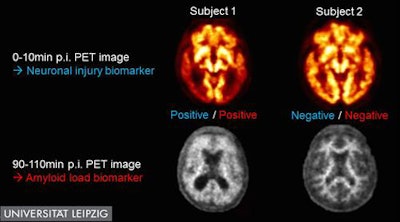

Images of PET with dual-time-point florbetaben radiotracer of two cognitively impaired subjects. While subject No. 1 (left) was judged as positive for both neuronal injury and amyloid load biomarker, both Alzheimer's disease biomarkers were negative in subject No. 2 (right). Image courtesy of Henryk Barthel et al, University Hospital Leipzig, Leipzig, Germany.The group believes the findings indicate that dual-time-point F-18 FBB PET could supplement diagnostic dementia workups by providing essential information about Alzheimer's pathology in a convenient and clinically useful manner, the SNMMI reported in a press release.

Researchers from University Hospital Leipzig in Germany performed dual-time-point PET scans with an F-18 florbetaben (FBB) radiopharmaceutical. The scans involve the injection of a single dose of the radiotracer, after which two scans are performed, one to observe blood flow and the other to measure the amyloid burden in the brain -- both of which are markers for neurodegenerative disease.

The group studied 112 individuals with an age range of 62 to 82 years: 41 were diagnosed with mild cognitive impairment, 50 had probable or possible Alzheimer's disease, and 21 had another type of dementia. PET scans with the dual-time-point F-18 FBB protocol were performed during the first 10 minutes of the procedure and again from the 90- to 110-minute mark.